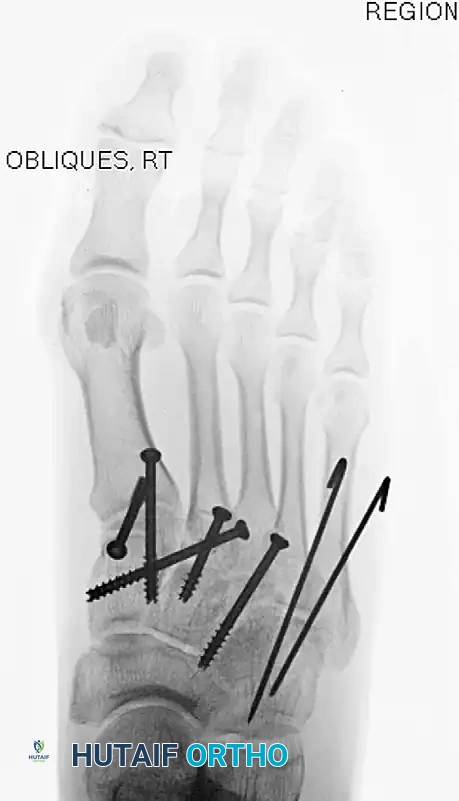

2. Medial Column Reduction (1st TMT)

- Reduce the first tarsometatarsal joint anatomically.

- Hold the reduction provisionally with K-wires or a pointed reduction clamp.

- Place a 4.0-mm cannulated or solid cortical screw from the dorsal aspect of the first metatarsal base into the medial cuneiform. A second screw can be placed from proximal to distal across the joint for rotational stability.

3. The "Homerun" Screw (Lisfranc Articulation)

- Under fluoroscopic guidance, reduce the second metatarsal base into its keystone slot between the cuneiforms. Hold this with a towel clip or reduction forceps.

- Pass a guidewire from the medial aspect of the medial cuneiform, aiming laterally and distally into the base of the second metatarsal. This trajectory mimics the native Lisfranc ligament.

- Overdrill and place an appropriate 4.0-mm or 4.5-mm cannulated screw over the guidewire to compress the interval.

4. Central Column Fixation (2nd and 3rd TMT)

- The second and third metatarsal-cuneiform joints are reduced and fixed similarly, typically with a single screw across each joint from dorsal-distal to plantar-proximal.

- If an intercuneiform screw is needed to stabilize the cuneiform complex, insert it under fluoroscopic guidance from the medial side of the medial cuneiform into the middle cuneiform.

6. Lateral Column Stabilization (4th and 5th TMT)

The fourth and fifth TMT joints are highly mobile and essential for accommodating uneven terrain. Rigid screw fixation here is contraindicated as it leads to stiffness and hardware failure.

* Reduce lateral metatarsocuboid disruptions either closed or open through the dorsolateral incision.

* Fix provisionally with smooth K-wires (Steinmann pins) driven from the metatarsals into the cuboid. These are left protruding or buried just under the skin for easy removal at 6 weeks.